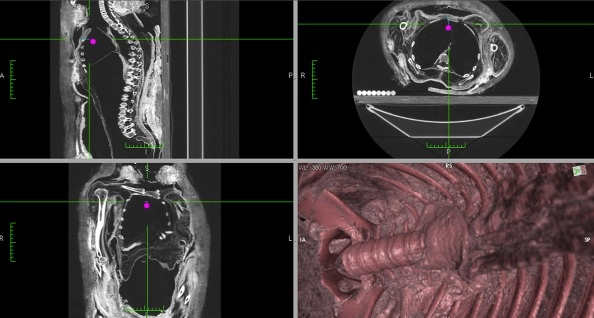

To see how eviscerations really took place, Wade and his colleague Andrew Nelson looked through the literature, finding details on how 150 mummies were embalmed over thousands of years in ancient Egypt. They also conducted CT scans and 3D reconstructions on seven mummies.